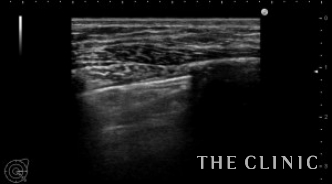

本日は横浜院でヒアルロン酸のしこり除去を行いました。

4年前にヒアルロン酸豊胸をしましたが、両側の乳房に8cm大のしこりになったため相談に来られました。

局所麻酔後、穿刺してヒアルロニダーゼを注入して吸引します。

ヒアルロン酸注入によるしこりのエコー診断カルテ